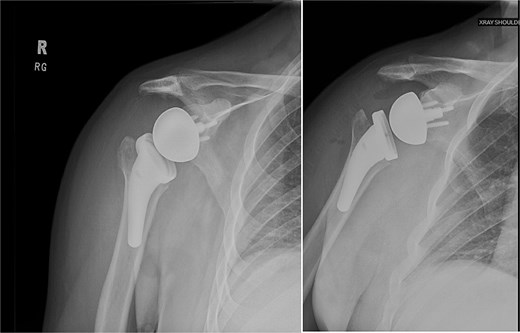

At 2 years after the initial injury, he continued to have right shoulder dysfunction, with forward flexion limited to 120°, external rotation limited to 30° with his arm at his side, and notable weakness with resisted external rotation at 4/5 strength despite injections, physical therapy, and arthroscopic debridement. Ultimately, he underwent rTSA with concurrent latissimus dorsi tendon transfer to address external rotation deficits associated with his posterior cuff deficiency. The subscapularis was additionally repaired using a medialized transosseous construct. He was maintained in an immobilizer for 6 weeks and then started formal therapy (Fig. 9).

Right reverse total shoulder arthroplasty at 3-month postoperative follow-up.

Two and a half years after injury, the patient reported continued improving function. He achieved a Disabilities of the Arm, Shoulder and Hand score of 56. Left and right shoulder range of motion measured 151° and 156° in forward flexion, 135° and 130° in abduction, and 38° and 66° in external rotation, respectively. He was independent with a home exercise program and had resumed household and outdoor activities, however, had not returned to work. His left shoulder remained more symptomatic, with activity-related discomfort and pain up to 4/10.